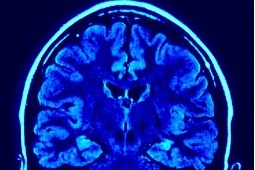

Czy przerzuty nowotworów zarodkowych do mózgu można leczyć samą chemioterapią?

Nowotwory zarodkowe są najczęstszymi nowotworami  złośliwymi u młodych mężczyzn. W zależności od typu histologicznego oraz zaawansowania choroby kwalifikujemy chorych do jednej z trzech grup rokowniczych. W przypadku przerzutów odległych w narządzie innym niż płuco mamy do czynienia z grupą chorych o złym rokowaniu.